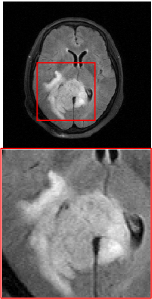

Figure 5 provides the qualitative comparison of the various methods on the four datasets at a scale of 4. The top, second, third, and bottom rows are the SR results under the FastMRI, clinical brain, clinical tumor and clinical pelvic datasets, respectively. The red boxes indicate the zoom-in region of complicated anatomical structures along with their corresponding error maps. Note that the brighter textures in the error maps, the lower the quality of the reconstructed images. As can be seen, compared to methods based on Transformers and CNNs, diffusion-based methods like DisC-Diff and DiffMSR (Ours) are capable of reconstructing high-realistic images with promising reconstruction metric scores (PSNR and SSIM). Nevertheless, while DisC-Diff can reconstruct high-precision MR images, it does not preserve the structure present in the original HR images, introducing some additional information that can affect medical diagnosis. In contrast, our method combines DM and PLWformer, which can preserve the original image’s structure while restoring high-frequency information.

Effect of Condition. To evaluate the effect of the condition extraction module, we design a variant by removing CE (named as w/o CE), which means that condition is not employed in the denoising process, as shown in Table 2. As can be seen, without condition , the reconstruction performance decreases, which demonstrates that condition extracted by the CE can provide supplementary information for the denoising network. Besides, Figure 6 provides a qualitative comparison w/o CE. As can be seen, without condition , the reconstructed image will lose some complicated anatomical structures.

In this section, we present more visual qualitative comparisons. Figures 8, 9, 10, and 11 show the reconstruction results of each method in FastMRI, clinical brain, clinical tumor, and clinical pelvic, respectively. As can be seen, although DisC-Diff can reconstruct MR images with high-frequency information, it fails to preserve the structure and content of the original Target HR image effectively, resulting in image distortion. In contrast, our proposed DiffMSR can restore high-frequency information while preserving the structure of the original HR image, indicating the effectiveness of the joint use of DM and PLWformer.